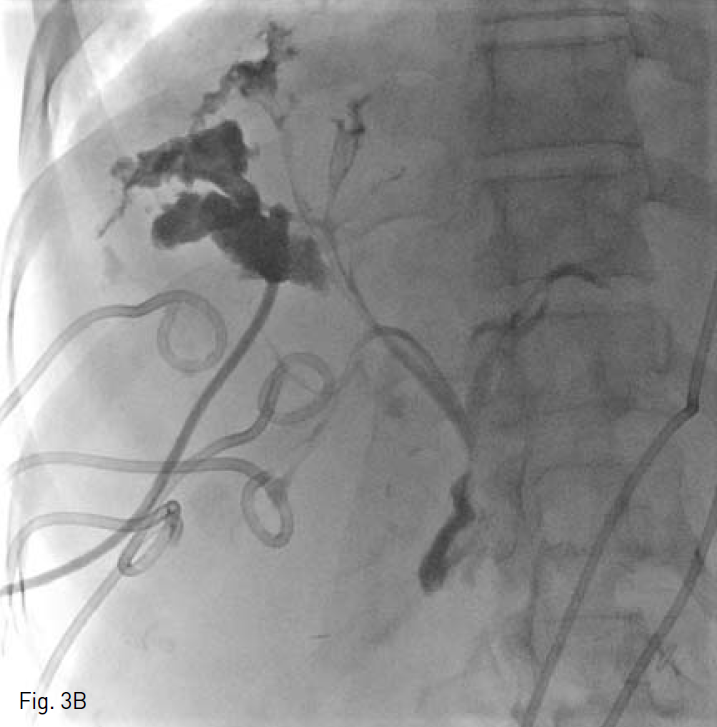

Fig. 3

Cholangiogram during right percutaneous biliary drainage A and cavitogram during percutaneous abscess drainage B show communications between abscess cavities and bile duct.